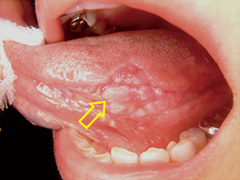

口腔癌の初期には以下のようなサインや症状が現れることがあります。

- 口腔内の潰瘍や白斑: 口腔内に白い斑点や潰瘍ができて、治らない場合は注意が必要です。